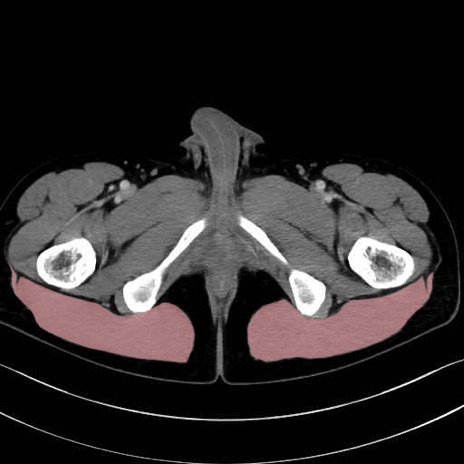

大殿筋(gluteus maximus)のCT画像の解剖

大殿筋 (Gluteus maximus)